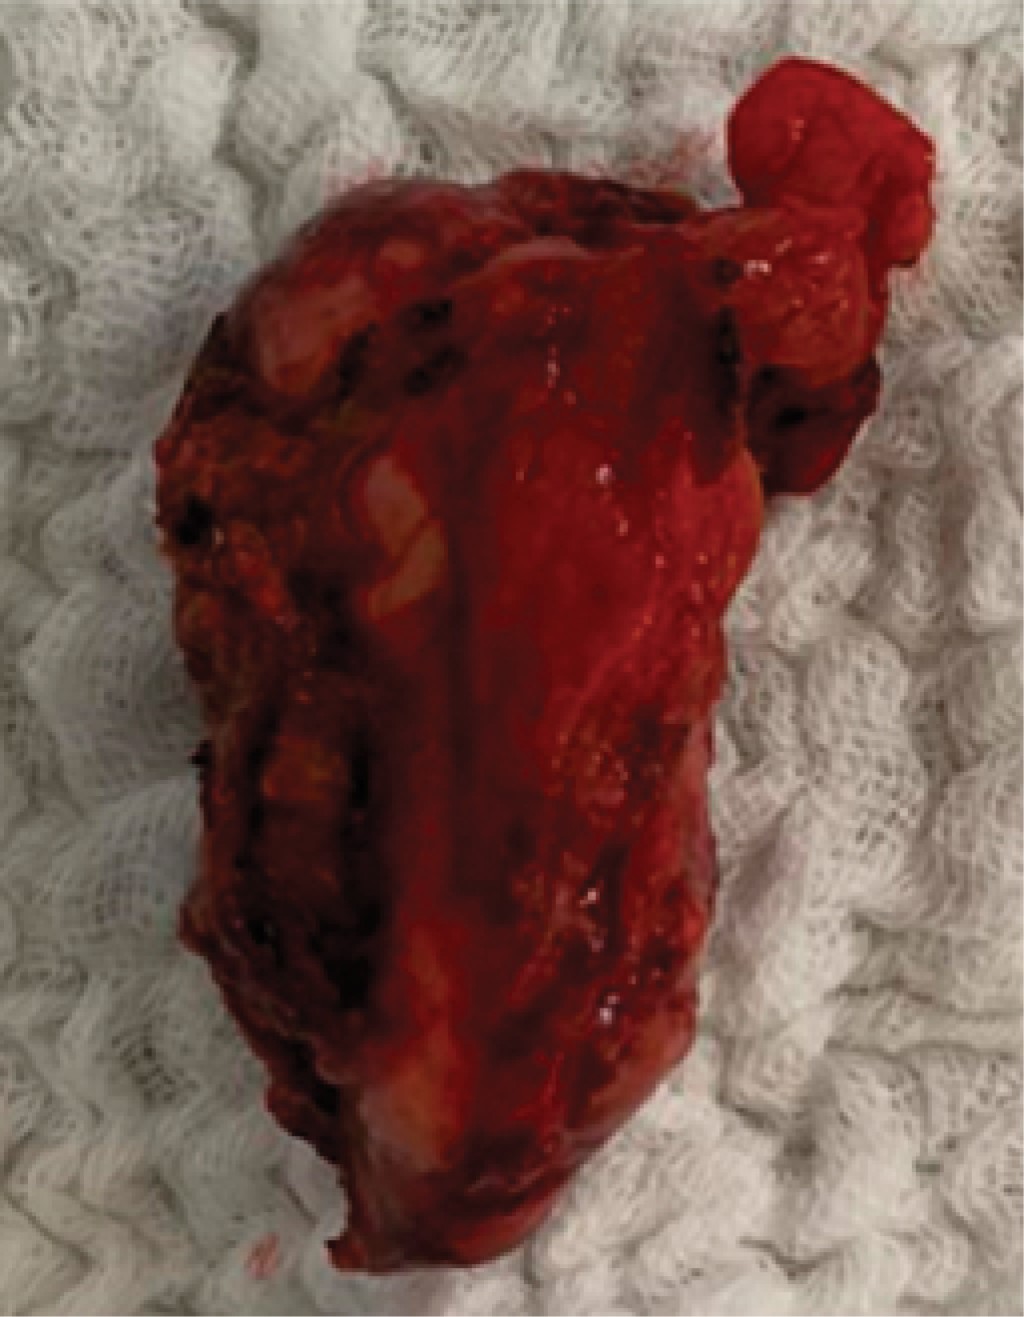

On physical examination, the patient was conscious and oriented; on admission, vital signs were heart rate of 92 per minute, blood pressure of 102/80 mmHg, oxygen saturation of 94% with FiO2 of 36%. The abdomen was distended with decreased hydroaerial sounds, and on palpation, there was evidence of involuntary muscle resistance with positive Dunphy's sign. Laboratory and imaging tests were performed with the following results: leukocytes: 14.7 K/µl, neutrophils: 77.7%, hemoglobin: 11.1 g/dl, hematocrit: 33.8%, platelets: 236,000 K/µl; arterial blood gases on admission showed a pH of 7.11, pCO2 of 36 mmHg, PO2 60 mmHg, HCO3 11.40 mEq/l, base excess -17.20 mEq/l, and lactate 9.70 mmol/l. It was decided to administrate crystalloid solutions and to perform a CT scan of the abdomen without contrast that showed a liver with a heterogeneous tomographic density of micronodular appearance, with a decrease in size of the right lobe, findings probably related to liver cirrhosis. In addition, perihepatic fluid in the perisplenic, and parietocolic gutters, and in the pelvic cavity was approximately 1,500 cm3 (Figure 1). Subsequently, the patient again refers a sensation of weakness with the following vital signs: heart rate of 115 per minute, and blood pressure of 80/50 mmHg, so it was decided to transfer him to the operating room urgently. A laparoscopic surgery was started, but due to the findings, it was decided to convert to laparotomy during the trans-surgical procedure, where 2,000 ml of hemoperitoneum were identified. The hemoperitoneum was drained and hepatic segmentectomy of segment II was performed (Figure 2); two red blood cell packages were transfused during the trans-surgical procedure. The patient was transferred to the general ward with hemodynamic stability; however, in the control examinations hemoglobin was found to be 8.5 g/dl, so it was decided to transfuse two more packs of red blood cells and two packs of fresh frozen plasma, after which his evolution was without complications. The Jackson Pratt drainage was removed and on the fourth day of hospitalization, he was discharged with oral paracetamol 1 gram every eight hours for five days.

Figure 2